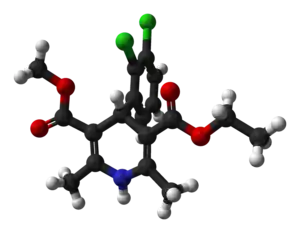

| Formula | C18H19Cl2NO4 |

| Molar mass | 384.25 g·mol−1 |

| 3D model (JSmol) | |

Felodipine is a member of the 1,4-dihydropyridine class of calcium channel blockers.[11]: 20–21 It is a racemic mixture, and is insoluble in water but is soluble in dichloromethane and ethanol.[11]: 25